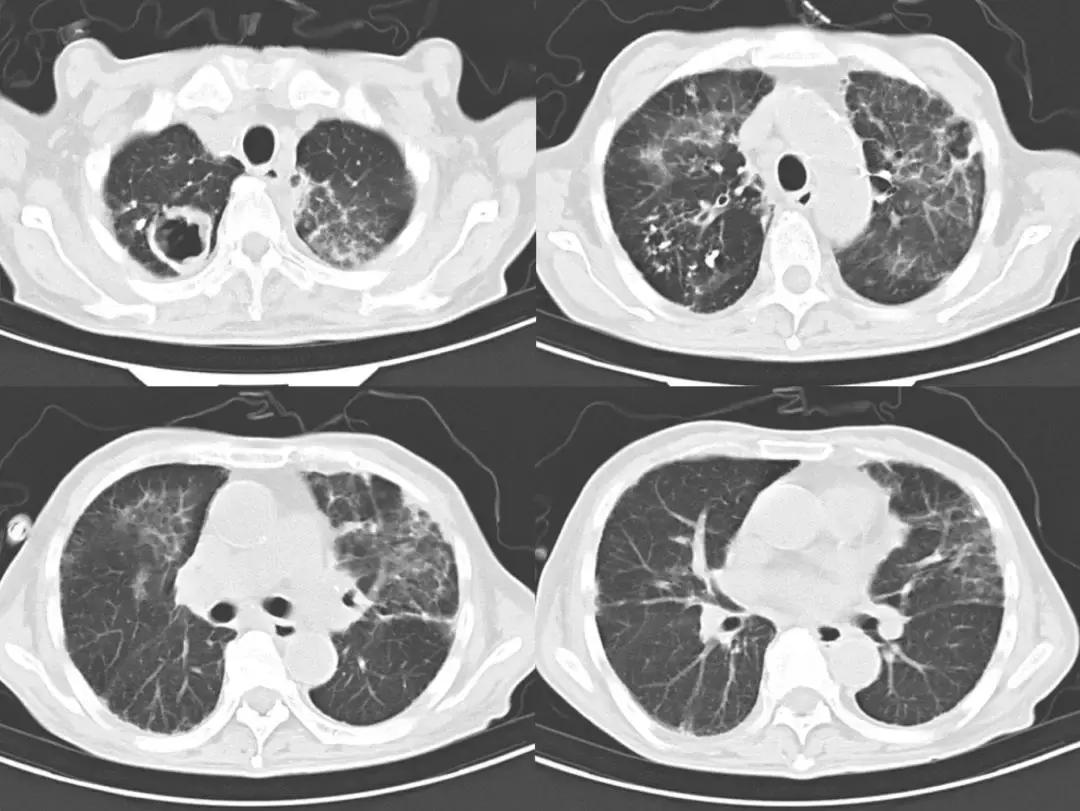

为进一步明确诊断,予以予以经皮胸腔穿刺抽液术,可见抽出黑色胸腔积液(图3)。胸腔积液mNGS结果回报:检出聚多曲霉 66个序列数。给予伏立康唑抗真菌治疗,患者咳嗽、咳痰明显好转,体温恢复正常。复查胸部CT(2018-8-25):肺部病灶较前明显好转(图4)。NGS结果回报后,通知检验科针对曲菌更改培养条件、延长培养时间,20多天后最终培养结果回报:聚多曲霉(图5)。患者出院后持续伊曲康唑抗真菌、正规抗结核治疗,未再出现发热,关节疼痛也明显好转,停用非甾体类止痛药和激素,随访中。

图4